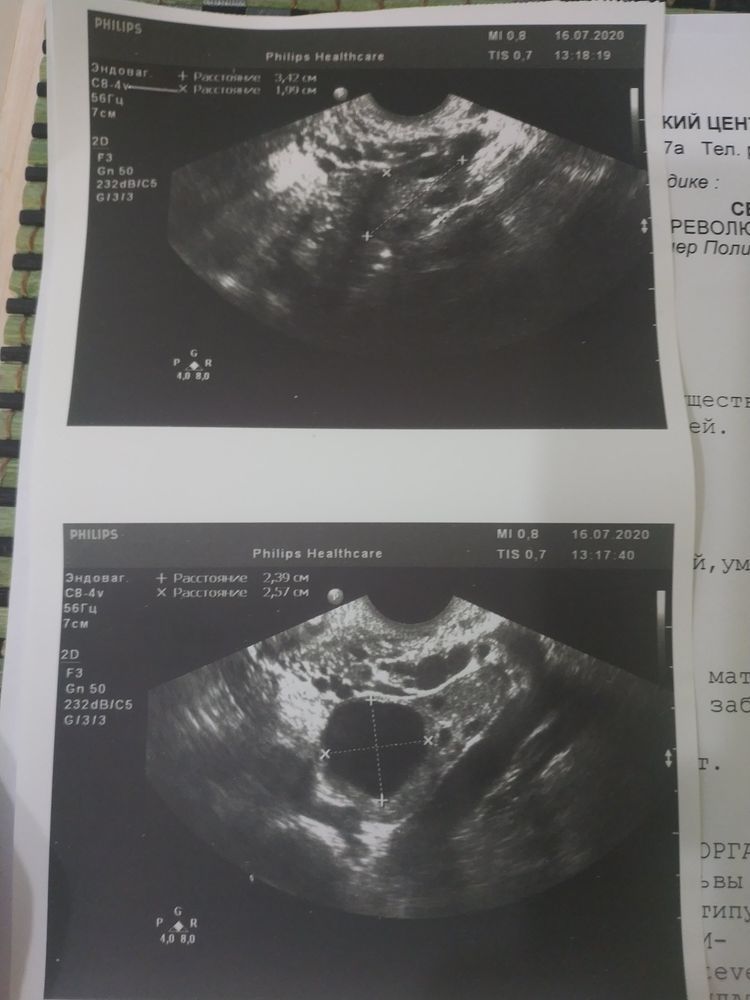

писала длинный пост, но он не сохранился, поэтому пишу коротко. Была на УЗИ сегодня, сказали есть плодное яцр, пустое. Месячные приходили во время, но были странные. Первый день месяца 6 июля. Цикл регулярный. Врач увидела овуляцию в левом яичнике. Сказала что беременность, кисты нет. Через неделю прийти повторно. Почитала интернет, и как бы засомневалась. Ведём ППА. Несколько лет. Не так давно планировали беременность но не получалось. Забили на это дело. И тут сидим и места не найдем).

Тест отрицательный. Фото с УЗИ прикладываю.

Если это ПЯ, то размер гораздо меньше, чем 1,5см. И насколько я поняла по фото, 1,5 см у вас в заключении узи указано совсем другое, возможно м-эхо. Размер очень маленький, чтобы гадать пустое оно или нет.

На последнем фото узи похоже выделено плодное яйцо (или что там) в 1,54см, это 15мм. Довольно большое. Сдайте хгч, в динамике. И тест уже должен быть положительный. Если оба анализа отрицательные, вновь идите к врачу.

Ну на узи жт и матка в которой что-то очень похоже на ПЯ. Но, это может быть и очаг эндометриоза.

Если это плодное яйцо, то размеры большие, для такого ПЯ уже должен быть эмбрион и тесты должны гореть полосками

Вообще на 1 фото очень много странных очагов 🤔